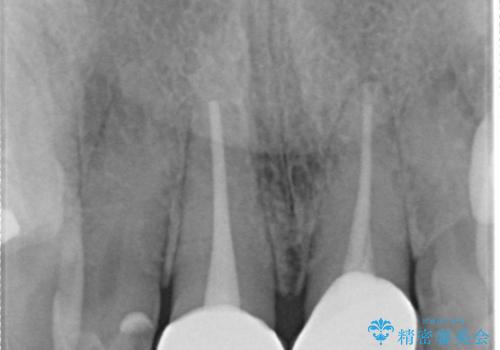

- 前歯の着色が気になるということを主訴に来院された患者様です。

以前に、根管治療をされているみたいなのですが、そのまま放置されていてどんどん着色がひどくなり来院されました。

神経の治療をしている歯は、時間と共に色がどんどん変色していきます。

また、神経、血液供給がなくなってしまうので歯も脆くなっていってしまう為、歯が割れてしまうリスクもあります。